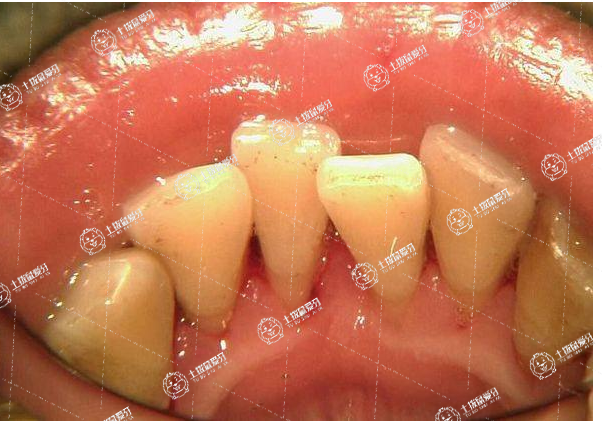

地包天的矯正首先建議患者先到醫(yī)院就診,明確診斷是骨性的、功能性的還是牙性的地包天,其治療過程如下:

1、功能性和牙性的地包天可以通過矯正,即戴牙套進行治療。戴牙套的過程中可能配合一些牽引或者種植釘?shù)容o助手段進行配合;

2、比較嚴重的骨性地包天,不能單純的通過戴牙套矯正的,還是建議患者進行正頜手術(shù)。正頜手術(shù)之前要進行術(shù)前的正畸治療,主要是調(diào)整牙齒的角度;正頜手術(shù)后還要進行正畸治療,通常是調(diào)整精細咬合。